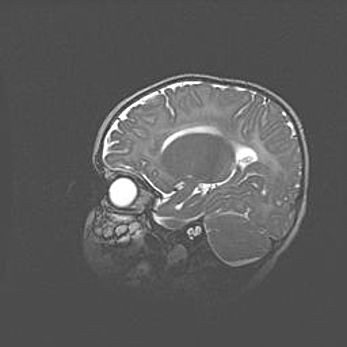

Церебральная ишемия II.

Возраст: 5 дней

Вес: 3400 г

Пол: женский

Окружность головы: 35 см

Срок гестации: 39 недель

Церебральная ишемия – это заболевание, характеризующееся недостаточностью (гипоксией) либо полным прекращением (аноксией) снабжения мозга кислородом по причине закупорки одного или нескольких сосудов. Это приводит к  что метаболическим расстройствам различной степени тяжести в тканях головного мозга, развитию коагуляционных некрозов и гибели нейронов.